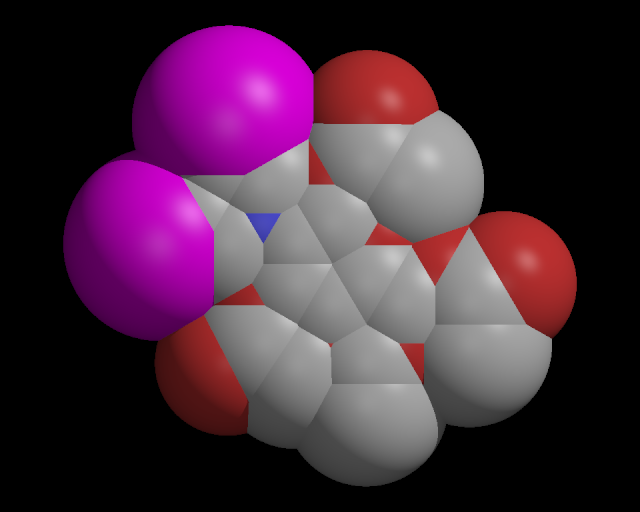

669440 1,3,4,6-Tetra-O-acetyl-2-(di-2-chloroethyl)amino-2-deoxy-D-g lucopyranose 2-Deoxy-2-(di-2-chloroethyl)amino-1,3,4,6-tetra acetoxy-D-glucopyranose 4-18-00-07550 (Beilstein Handbook Re ference) 56879-48-2 BRN 0099172 Glucopyranose, 2-deoxy-2-(di -2-chloroethyl)amino-1,3,4,6-tetraacetoxy-, D- NSC-344281 Te traacetylglucosamine mustard Smiles: ClCCN(CCCl)C1C(OC(=O)C)OC(COC(=O)C)C(OC(=O)C)C1OC(=O)C pdb file: 669440.pdb sdf file: 669440.sdf

Please note: images may show incorrect connectivity due to improper geometry. We will be working to improve this situation. For now, the left image should be correct, and the other two are correct, if they match the first. Image Links Molecule Name Links